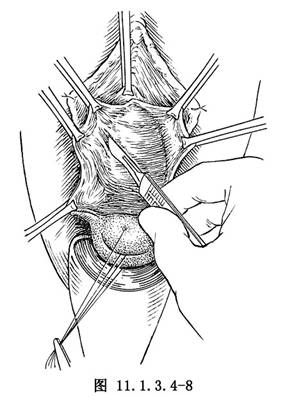

(2)用鼠齒鉗夾住切開的陰道黏膜,向外側牽引,以紗布纏手指,剝離陰道壁,接近尿道外口,尿道與陰道壁粘連緊,可用尖刀銳性剝離,達尿道兩側深處,顯露膀胱頸部(圖11.1.3.4-8)。如不清楚,從尿道外口插入一帶氣囊的導尿管、充氣後牽引導尿管,遇到阻力處,即爲膀胱頸。